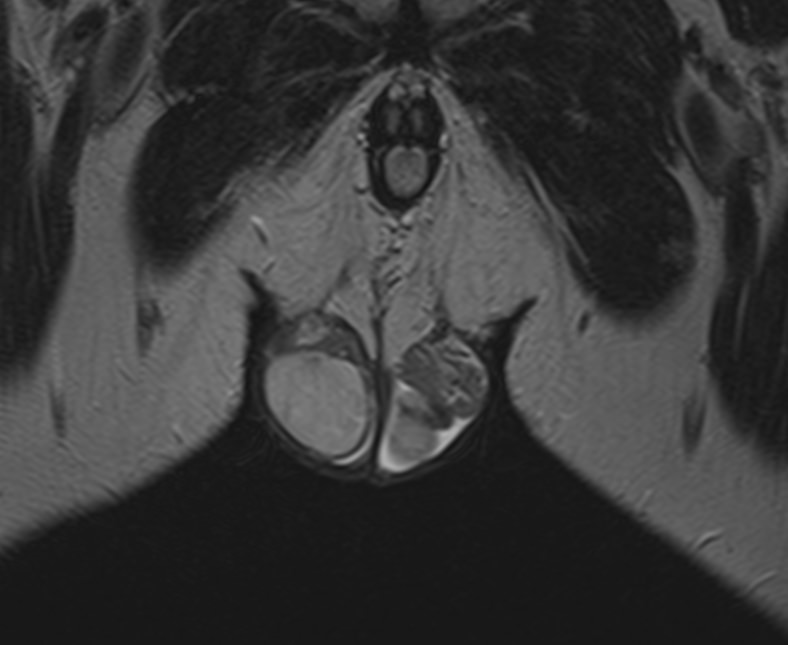

Метод позволяет диагностировать патологию мужских половых желез (яичек), их придатков и семявыносящих протоков. Эти органы, вместе с кровеносными сосудами, лимфатическими протоками и нервами, располагаются в мошонке – мешотчатом образовании из гладких мышц и кожи.

Во время исследования производится послойное сканирование в трех взаимно перпендикулярных плоскостях с шагом от 1 мм, в дальнейшем с помощью инновационных приложений аппарат трансформирует полученные данные в трехмерные изображения. Методика позволяет выявлять структурные изменения органов мошонки на самой начальной стадии. Особенно это важно для диагностики опухолей.

При подозрении на развитие объемных образований, для проведения дифференциальной диагностики, может применяться контрастное усиление. В таких случаях, пациенту внутривенно вводится контрастный препарат, содержащий гадодиамид (соли металла гадолиния), который способен «высвечивать» патологические очаги при попадании в зону действия магнитного поля томографа. С помощью контрастирования удается выявлять опухоли размером от 1 мм. Ранняя диагностика онкозаболеваний позволяет вовремя назначить необходимое лечение.

После того, как исследование окончено, задачей врача является расшифровка полученных снимков. Чаще всего удается определить следующие патологические процессы:

• Аномалии строения органа;

• Злокачественные или доброкачественные новообразования;

• Фиброзные изменения кавернозных тел;

• Сосудистые патологии, в том числе варикоцеле;

• Водянка яичка;

• Наличие абсцесса;

• Пневматоз;

• Склероз яичек;

• Крипторхизм;

• Воспалительные процессы;

• Аденомиоз;